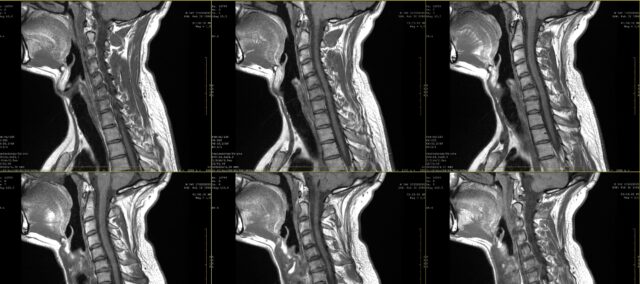

På skolen har du sikkert lært om smertetegninger for radikulær smerte. Allerede i det første tiåret av det 21. århundre ble det imidlertid klart at radikulær smerte ikke nødvendigvis følger en dermatomal fordeling. Denne studien ønsket å se nærmere på samsvaret mellom visuell inspeksjon av radikulære smertetegninger som bemerket av pasienter og MR. I praksis uttrykker ofte en pasient sine plager, og dette kan suppleres med en smertetegning. Når det er mistanke om radikulær smerte, foreskrives ofte medisinsk bildediagnostikk for å bestemme den berørte nerveroten og omfanget av mulig nerverotinvolvering. Selv om dette i mange tilfeller gjør en del av rutinepraksis, vet vi ikke før vi vet samsvaret mellom disse smertetegningene og den berørte nerveroten bestemt ved bruk av MR. I denne studien har Marco et al. (2023) sammenlignet radikulære smertetegninger og MR-funn.

For å undersøke samsvaret mellom radikulære smertetegninger og MR-funn, inkluderte denne studien deltakere med en 2-måneders historie med vedvarende smerte, som ble diagnostisert med cervikal radikulopati på MR. Denne diagnosen ble stilt av en nevrokirurg basert på klinisk informasjon og MR-funn vurdert av en radiolog.